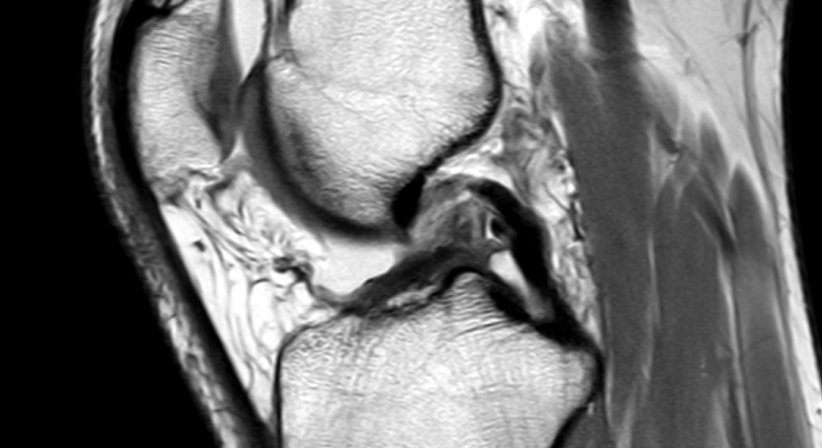

Von einem Kreuzbandriss, auch Kreuzbandruptur genannt, spricht man bei einem unvollständigen (partiellen) oder vollständigen (kompletten) Riss (Ruptur) eines oder beider Kreuzbänder. In den meisten Fällen ist das vordere Kreuzband (Ligamentum cruciatum anterius) von einem Riss betroffen.

Kreuzbandrisse entstehen meist ohne Fremdeinwirkung durch plötzliche Richtungswechsel beim Laufen oder Springen. Sie sind die häufigsten klinisch relevanten Verletzungen im Bereich des Kniegelenks. Kreuzbandrisse können anhand ihrer Symptome, der Beschreibung des Verletzungsvorgangs und mithilfe einfacher manueller Untersuchungen relativ sicher diagnostiziert werden. Mit einer Magnetresonanztomografie (MRT) kann die Diagnosestellung weiter abgesichert werden.